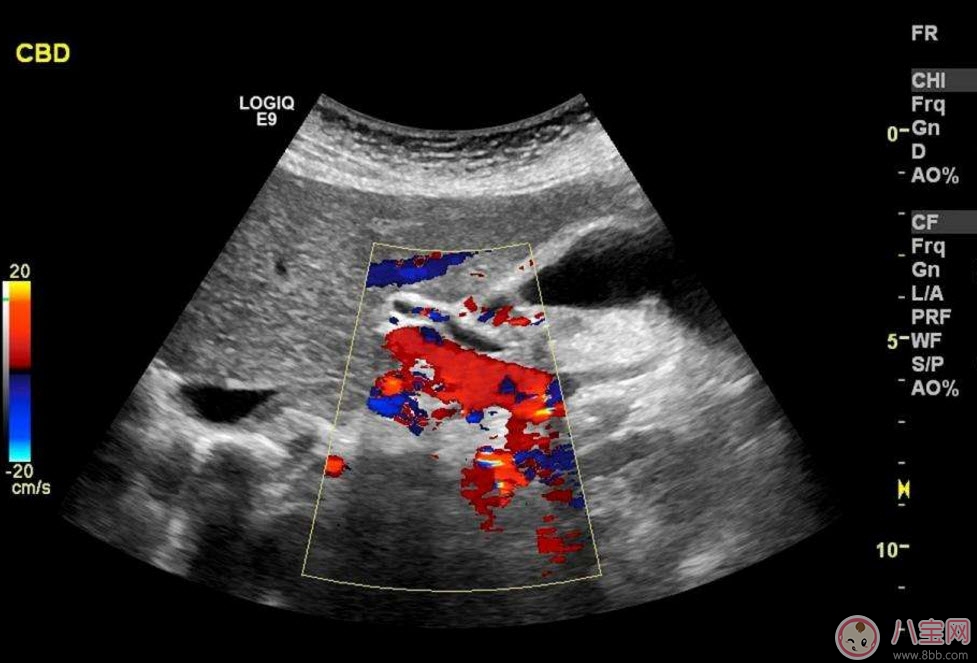

除了能觀察到通過(guò)B超觀察到的一切外,彩超能夠直觀成像,顯示更清晰,結(jié)果也更快速,可發(fā)現(xiàn)異常血流,為診斷胎兒先天性心臟缺陷提供了診斷依據(jù)。價(jià)格要比B超貴,大概在150元左右(會(huì)根據(jù)各地具體情況的不同而上下浮動(dòng))。二維彩超適用于整個(gè)孕期,特別是臨產(chǎn)前。二維彩超的圖像也并非就是彩色的,而是用彩色標(biāo)注心臟、血流等指標(biāo),其實(shí)就是高清晰度的黑白B超再加上彩色多普勒。觀測(cè)到的圖像以紅藍(lán)兩色血流方向?yàn)橹?,面向探頭的呈現(xiàn)紅色,反之為藍(lán)色。這種技術(shù)能夠觀測(cè)到胎兒的血液流動(dòng)情況,有利于及時(shí)發(fā)現(xiàn)胎兒的異常。比如,發(fā)現(xiàn)胎兒頸部有血流環(huán),則意味著發(fā)生了可導(dǎo)致窒息死亡的臍帶繞頸。

??B超也稱為二維超聲,分為黑白的和彩色的兩種。 彩超其實(shí)還是黑白的,彩超簡(jiǎn)單的說(shuō)就是高清晰度的黑白B超再加上彩色多普勒,既具有二維超聲結(jié)構(gòu)圖像的優(yōu)點(diǎn),又提供了血流動(dòng)力學(xué)的豐富信息。彩超的分辨率會(huì)比一般黑白B超高一些,所以在需要做比較細(xì)致的檢查的時(shí)候,更多的醫(yī)生愿意通過(guò)彩超來(lái)檢查。例如,因?yàn)椴食苡貌噬珮?biāo)注血流,所以當(dāng)臍帶繞頸的時(shí)候就會(huì)看見(jiàn)寶寶的脖子上呈U形或者W形的血流,對(duì)是否臍帶繞頸也就一目了然了。目前用于產(chǎn)檢的超聲波一般都是二維的。